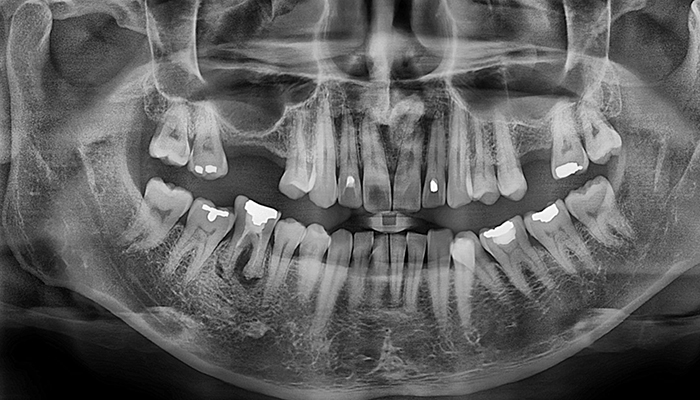

임플란트 수술시, 상악동과 잇몸뼈 사이에 뼈가 남아 있지 않았을 때 상악동막을 들어올리고 빈 공간에 뼈를 이식하여 임플란트 식립을 위한 공간을 확보하는 수술을 상악동 거상술이라 합니다.

밀도가 높고 두꺼운 턱뼈가 구성된 아래턱과는 달리 위턱은 얇은 뼈 위에 코와 광대 사이 빈 공간에 식립해야 하는 고난도 수술로 임플란트 수술 경험이 많은 의료진에게 받는 것이 중요합니다.

• 위 턱 잇몸뼈의 상태가

안 좋은 경우

• 위 어금니 잇몸뼈

높이나 넓이가 부족한 경우

• 치아가 빠지고 오래 방치해

잇몸뼈가 녹은 경우

• 임플란트를 식립해야하는

위치의 뼈가 물렁물렁한 경우